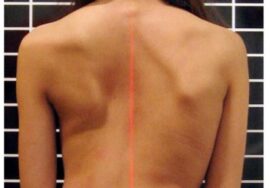

كيف تكتشف اعوجاج العمود الفقري مبكرًا عند طفلك؟

من المهم أن يكون الأهل على وعي بالعلامات المبكرة، ومنها:

تفاوت في مستوى الأكتاف.

بروز أحد جانبي الصدر أكثر من الآخر.

ميل الجسم إلى أحد الجانبين.

عدم تساوي الخصر أو الوركين.

في حال ملاحظة أي من هذه العلامات، يجب استشارة الطبيب على الفور لعمل فحص سريري وتصوير بالأشعة إذا لزم الأمر.